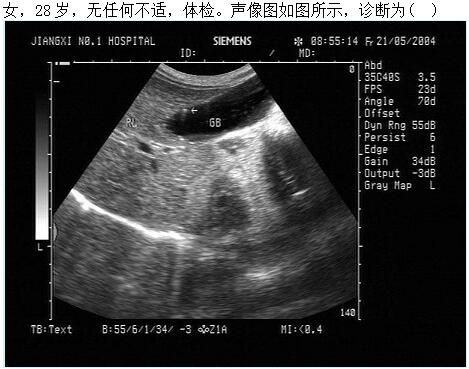

A.胆囊结石

B.胆囊息肉

C.胆囊胆固醇结晶

D.胆囊腺瘤

E.胆囊癌